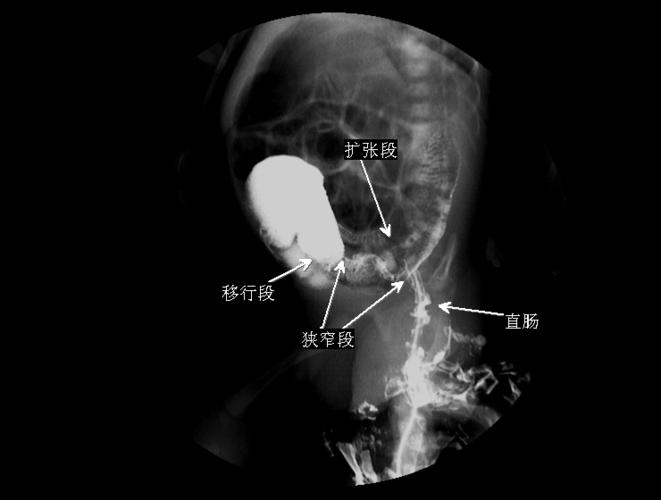

肠梗阻片子,肠梗阻ct

x 线片多可发现肠腔充气扩张或低位肠梗阻,造影显示典型的狭窄段,扩张